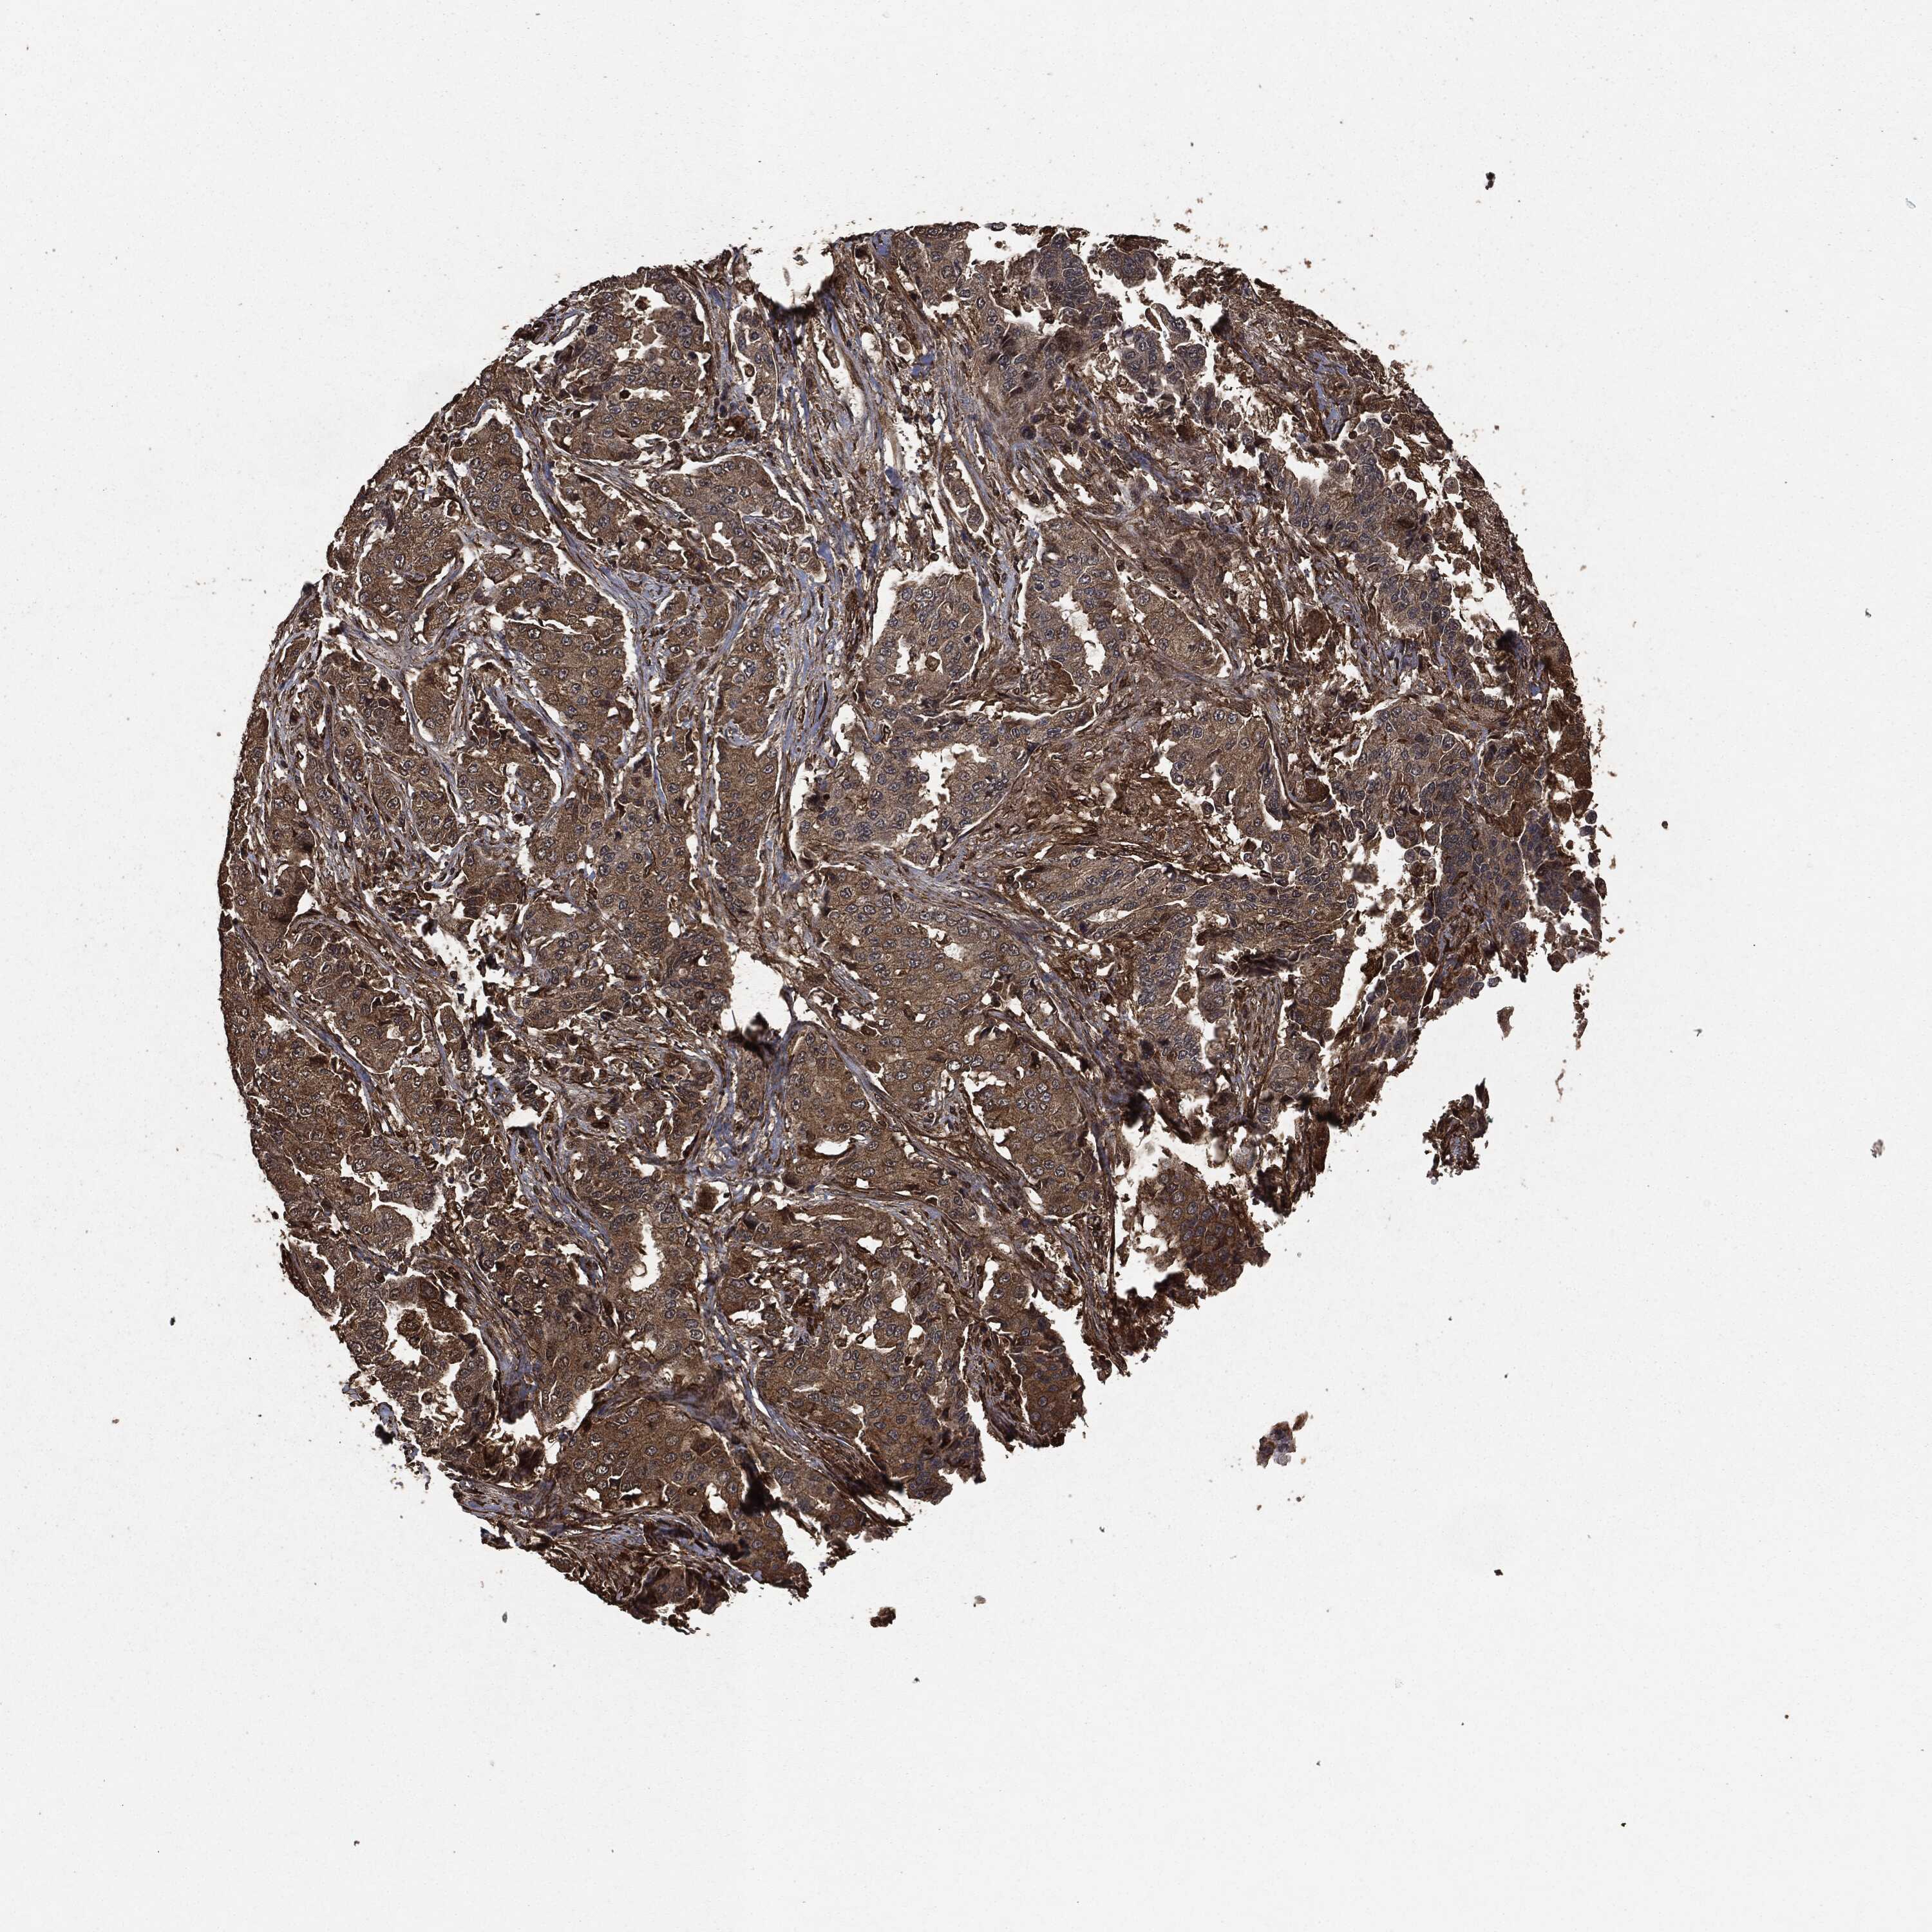

CANCER LUNG CANCER Show tissue menu

LUAD TCGA LUAD VALIDATION LUSC TCGA LUSC VALIDATION PROTEIN LUAD CPTAC PROTEIN LUSC CPTAC PROTEIN EXPRESSION